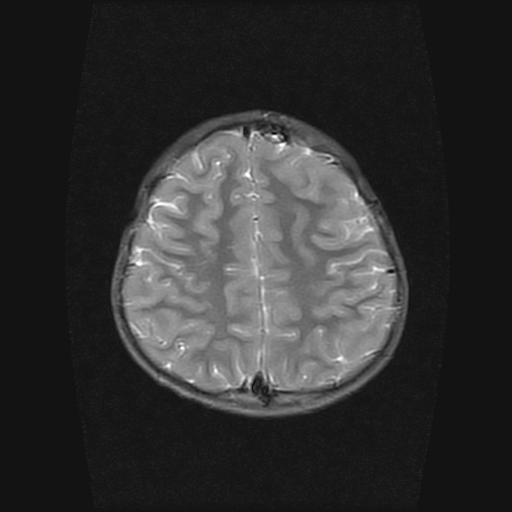

6岁小儿,左侧视神经瘤术后。现左侧视力减退。